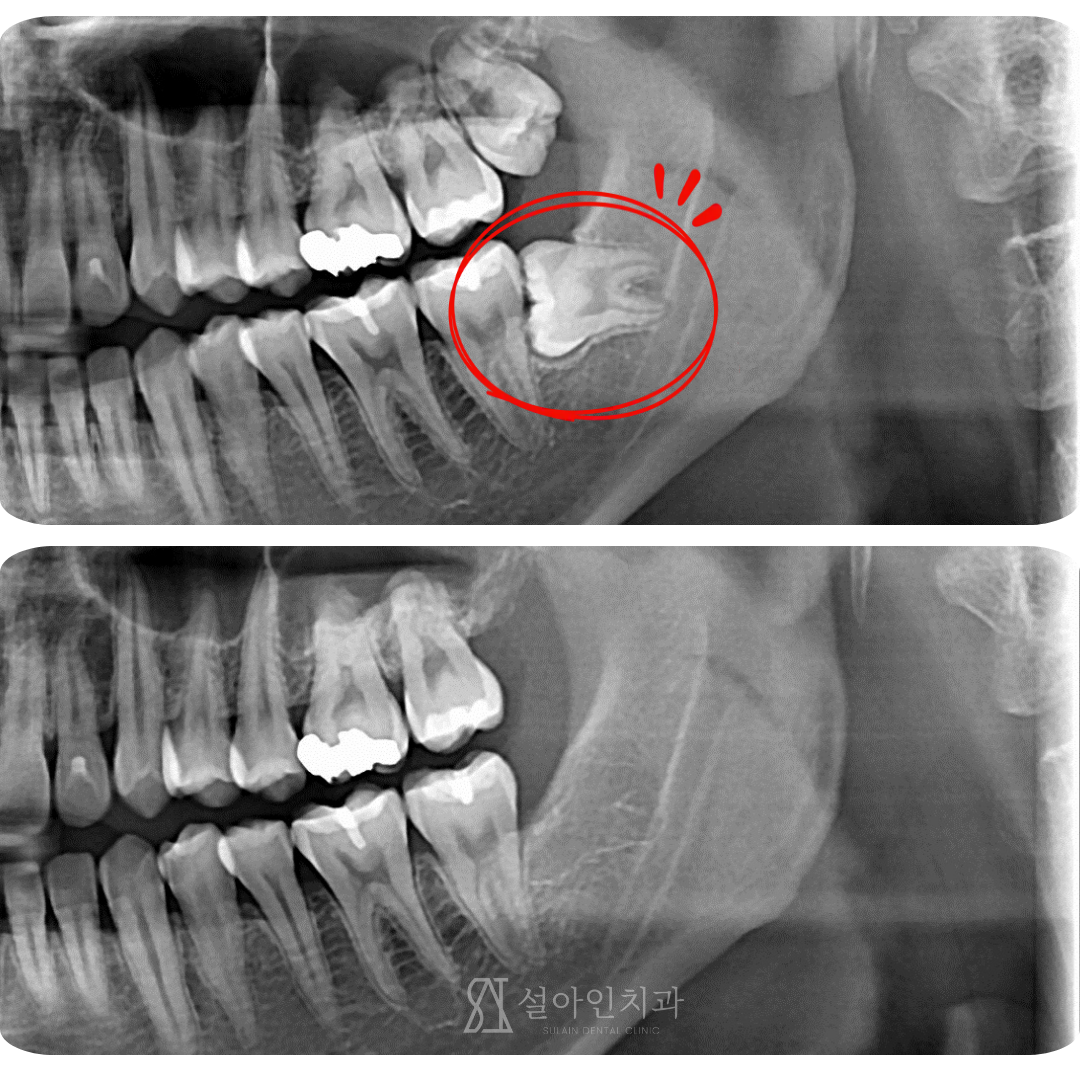

가로로 누워 자란 사랑니, 난이도 높은 수술도 안전하게 뽑을 수 있습니다.